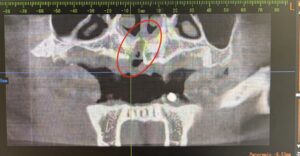

通常のレントゲンでは過剰歯の正確な位置や向き、周囲の神経・骨との関係までははっきりしませんでした😭

精密検査の一部CTデータを撮影することによって通常より多い歯(過剰歯)があごの骨の中に埋まっている状態が確認されました。

🦷過剰歯の正確な位置・深さ・方向が3Dで把握可能

🦷顎の骨や神経との距離も立体的に確認できる

🦷外科処置のリスク軽減や正確な治療計画につながる!

患者様のように埋伏過剰歯が骨の中に深く埋まっている場合でも、CTによって詳細な情報を得ることができます。